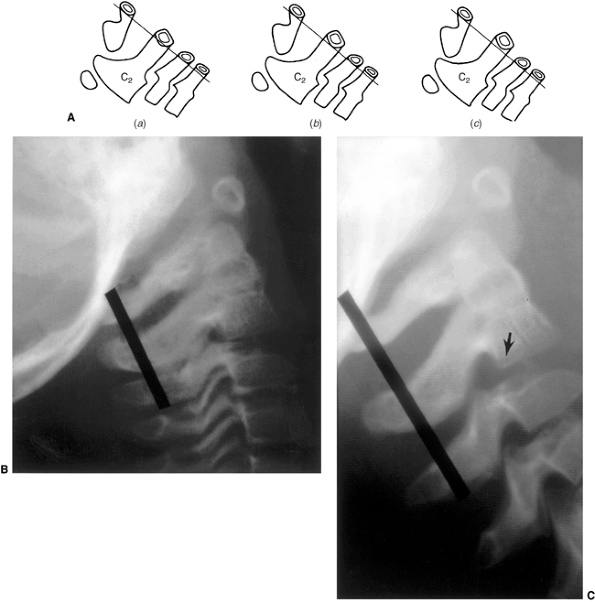

Figure 22.6 A: The posterior cervical line referred to by Swischuk. In C2-C3 pseudosubluxation, the posterior cervical line may pass through (a), touch (b), or lie 1 mm in front of (c) the cortex of the posterior arch of C2. B and C:

Lateral cervical radiographs of a child 2 years and 6 months of age with pseudosubluxation at C2-C3. The radiograph in extension (B) demonstrates no step-off at C2-C3, whereas the radiograph in flexion (C) demonstrates a step-off at C2-C3 (arrow), but with a normal posterior cervical line (solid line). Also note the anterior wedging of the C3 vertebral body, and the overriding of the anterior arch of the atlas on the tip of the odontoid in extension. (A from Shaw M, Burnett H, Wilson A, et al. Pseudosubluxation of C2 on C3 in polytraumatized children—prevalence and significance. Clin Radiol 1999;54:377–380, with permision.) |

pronounced that it appears pathologic (pseudosubluxation). In order to

differentiate physiologic from pathologic subluxation, Swischuk (41)

has proposed using, as a reference line, the posterior cervical line

drawn from the anterior cortex of the posterior arch of C1 to the

anterior cortex of the posterior arch of C3 (Fig. 22.6).

In physiologic displacement of C2 on C3, the posterior cervical line

may pass through the cortex of the posterior arch of C2, touch the

anterior aspect of the cortex of the posterior arch of C2, or come

within 1 mm of the anterior cortex of the posterior arch of C2. In

pathologic dislocation of C2 on C3, the posterior cervical line misses